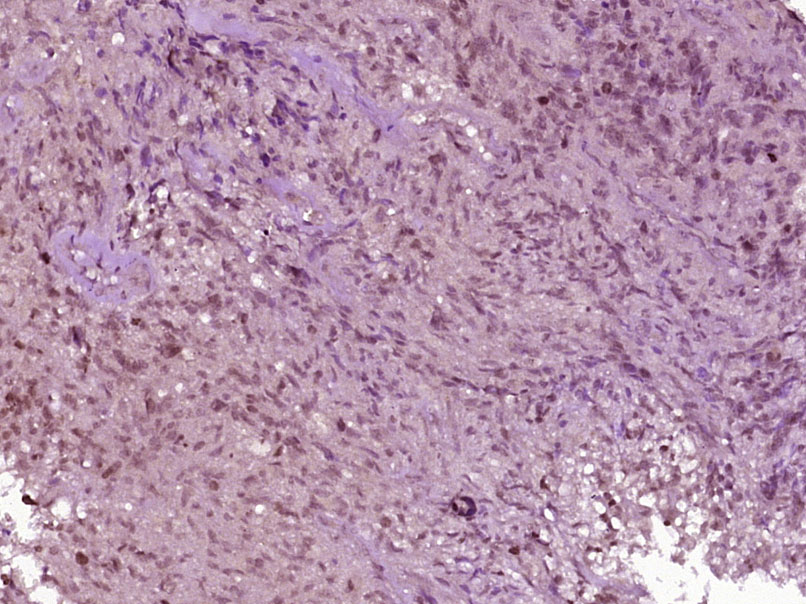

Paraformaldehyde-fixed, paraffin embedded (Human brain glioblastoma); Antigen retrieval by boiling in sodium citrate buffer (pH6.0) for 15min; Block endogenous peroxidase by 3% hydrogen peroxide for 20 minutes; Blocking buffer (normal goat serum) at 37°C for 30min; Antibody incubation with (phospho-Cofilin (Tyr89)) Polyclonal Antibody, Unconjugated (bs-5259R) at 1:400 overnight at 4°C, followed by operating according to SP Kit(Rabbit) (sp-0023) instructionsand DAB staining.